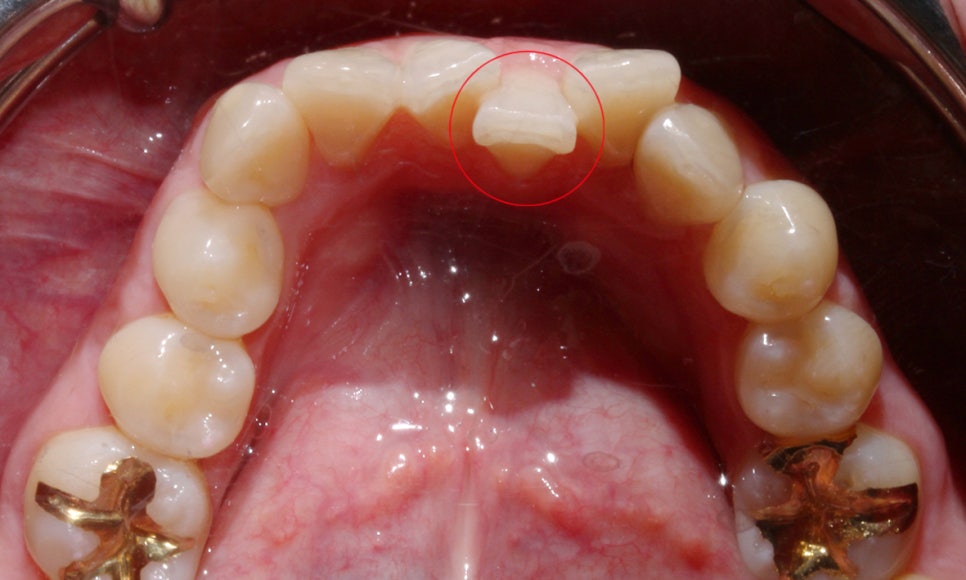

위의 사진은 상악 송곳니가

덧니로 자라난 Case로 덧니의

치아 높이를 보시면 주변 치열과 달리

확연하게 높은 위치로 벗어나 맹출된 것을

확인할 수 있습니다.